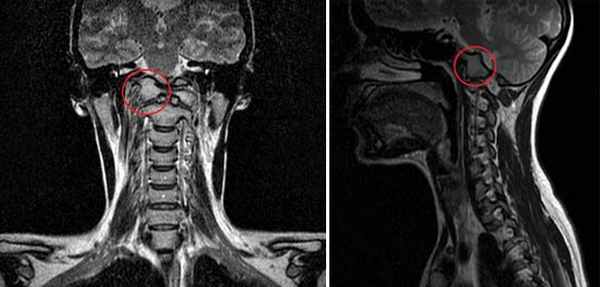

МРТ исследование пациентов с атланто-аксиальной сублюксацией

МРТ обеспечивает превосходное разрешение при исследовании нервной паренхимы и позволяет выявить другие патологии мозга, такие как дорсальную компрессию С1-С2, атланто-окципитальный оверлепинг, Киари и прочее.

Той терьер с атланто-аксиальной нестабильностью

На мрт исследовании нашего пациента – здесь представлена сагитальная Т2 взвешенная последовательность, определяется смещение аксиального позвонка в дорсальном направлении по отношению к атланту, дислокация дорсальной дужки атланта к задней черепной ямке с тяжелой компрессией как мозжечка, так и спинного мозга.